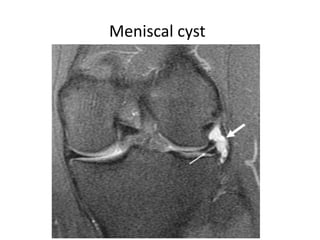

Meniscal cyst

• #37 - Fat-suppressed coronal T2-weighted MR sequence shows high-signal intensity meniscal cyst (large white arrow) with an associated oblique tear (small white arrow) in the body of the lateral meniscus. - When of average size, they are characteristically more prominent when the knee is extended and less prominent when the knee is flexed; small cysts may disappear within the joint on flexion (Pisani sign).